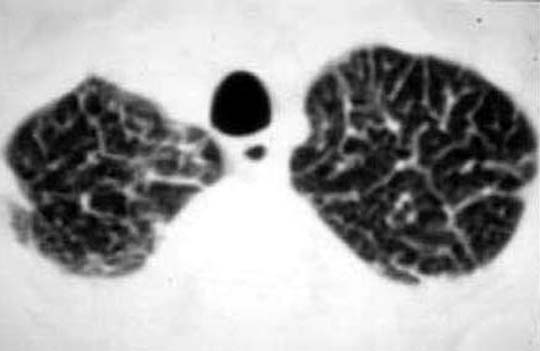

CXR